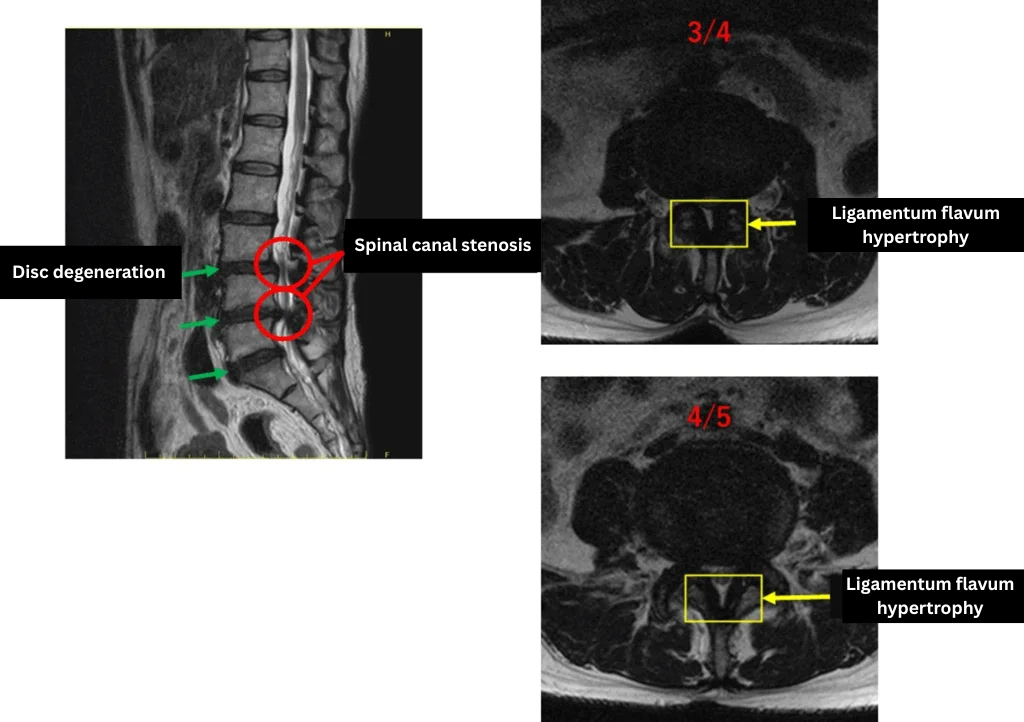

L1/2: no abnormality.

L2/3: mild disc degeneration

L3/4: disc degeneration, ligamentum flavum hypertrophy, spinal canal stenosis

L4/5: disc degeneration, ligamentum flavum hypertrophy, spinal stenosis.

L5/S: disc degeneration.

The above findings were also observed on the imaging.

・Findings at L3/4, L4/5, and L5/S indicate disc degeneration, ligamentum flavum hypertrophy, and spinal canal stenosis — likely the main cause of the patient’s symptoms.